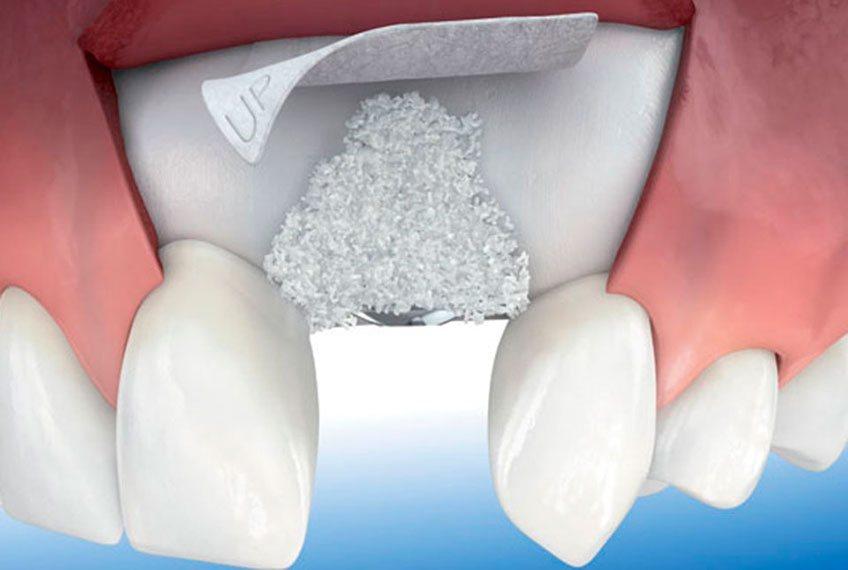

После удаления зуба происходит убыль костной ткани, поэтому очень важно проводить операцию по вживлению имплантата на место удаленного зуба либо непосредственно сразу после удаления зуба, либо в короткие сроки после удаления. Сильно отсроченная Имплантация или травматичное удаление всегда приводит к атрофии костной ткани и необходимости проведения костной пластики для увеличения объема кости и создания благоприятных условий для приживления имплантатов. На результат операции влияет квалификация и опыт врача, проводящего костную пластику, применяемые материалы и технологии.